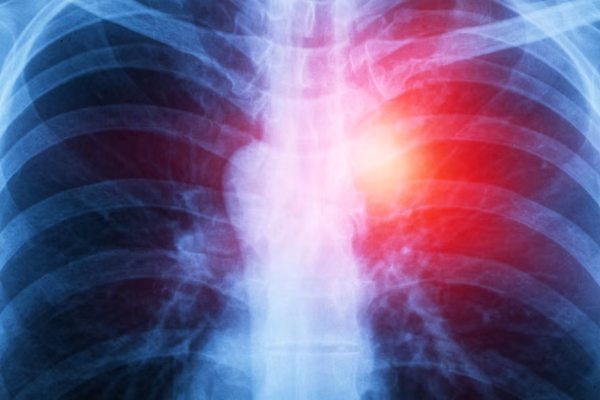

Mesothelioma is a rare, aggressive cancer. It affects the lining of the lungs, abdomen, or heart. Understanding mesothelioma is crucial for patients and their families. This guide aims to provide clear, concise information about the disease. You will learn about its causes, symptoms, and treatment options. Mesothelioma often results from asbestos exposure. Many people diagnosed…

Mesothelioma is a rare but serious cancer. It affects the lining of organs. Understanding mesothelioma is crucial for early detection and treatment. This blog provides essential information about this disease. You will learn about its causes, symptoms, and treatment options. Mesothelioma often results from asbestos exposure. This makes awareness important for prevention. Knowing the signs…

Mesothelioma is a rare and aggressive cancer. It affects the lining of the lungs, abdomen, or heart. For those diagnosed, self-care becomes crucial. It helps manage symptoms and improve quality of life. Understanding how to care for oneself can make a significant difference. Mesothelioma patients often face physical and emotional challenges. Daily routines, diet, exercise,…